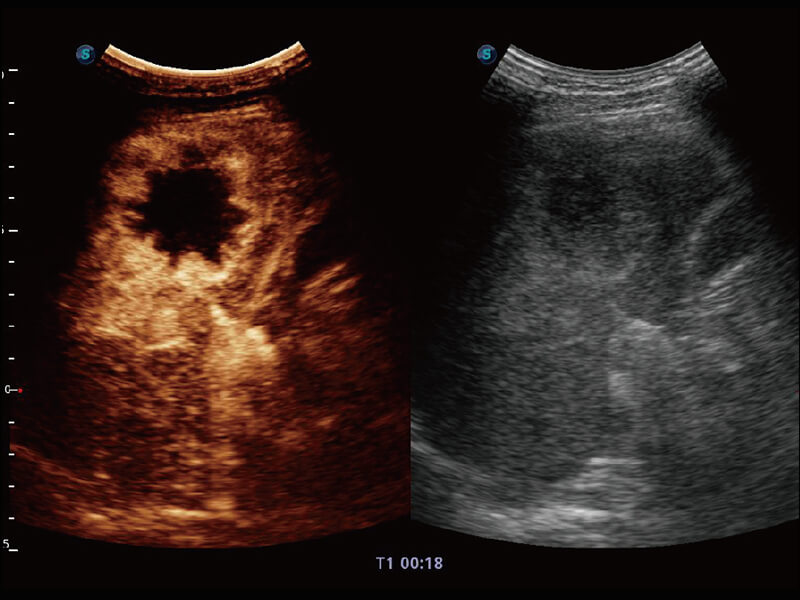

S60创新的探头工艺、高精度模数转换系统、前沿的波束重建技术,从前端信号处理每一个环节采集无损声学数据,真实还原组织原貌,再现解剖细节。

创新的超宽频带技术,为容积成像带来优质的二维图像基础,为您呈现更丰富的结构细节,栩栩如生地展示宝宝的宫内形态以及各种组织的立体结构。